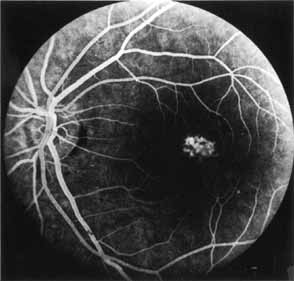

Although there is no reported genetic heterogeneity, there is wide phenotypic variation within the disorder. The major finding within the macula is a classic radial cystic maculopathy. Although retinal signs have been described in infants as young as 3 months, foveal schisis may be difficult to detect, leading to underdiagnosis. The diagnosis is usually not made until the affected male reaches school age (4 to 8 years of age) and encounters visual problems secondary to foveal involvement. Typical foveal schisis findings have been reported in 68% to 100% of eyes within various series.37,38 Foveal schisis is the only finding in about half the cases. It is characterized by the presence of radiate perifoveal microcysts located in the nerve fiber layer (Fig. 1) with radiate plications of the overlying internal limiting membrane that are seen especially well on monochromatic (red-free) photography (Fig. 2). The microcystoid change may slowly progress to form a macular cyst or hole. Foveal schisis has been reported in association with Goldmann-Favre vitreotapetoretinal dystrophy and rarely may be seen in rod-cone dystrophy or as an autosomal dominant or recessive condition.39–43

|